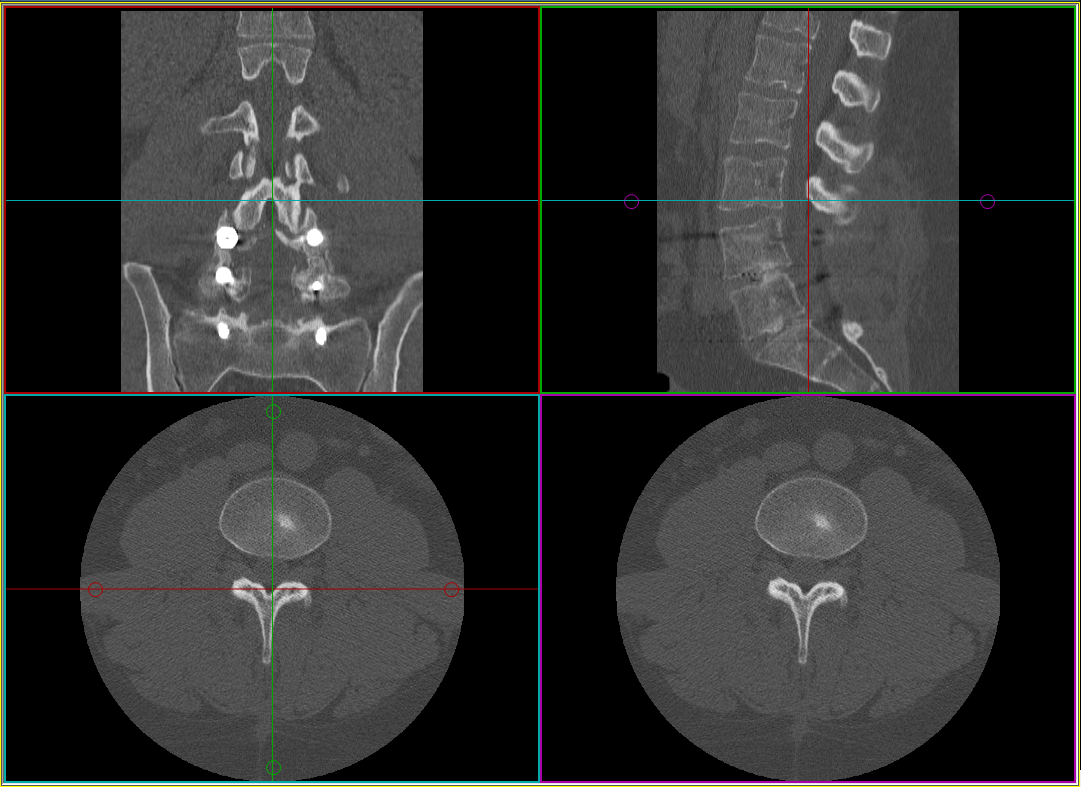

When the MPR frame is created, the image frame separates into four smaller frames. Each frame contains a single orthogonal view (sagittal, coronal, and axial) plus an oblique angle view. The oblique image frame is the results window, and is represented by the purple localizer in the coronal view. The other three frames are control windows. Color-coordinated localizers are available that match the color of the line to the color of the frame containing the image in that plane. Use these localizers to move and rotate the oblique image.

A rotate function is available on the oblique image frame to achieve a final desired presentation view.

Zooming and panning are also available functions for the oblique view.